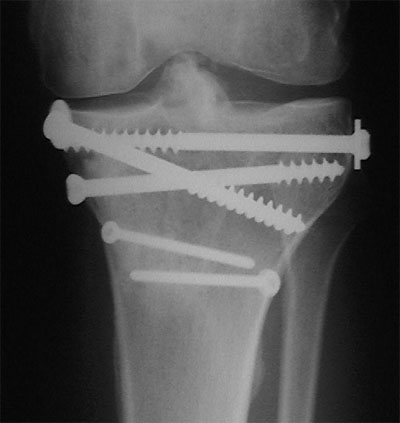

Die gute Nachricht: Im Röntgenbild vom 5. Juli sind kritische Bereiche des Kniegelenks wieder fast intakt, so z.B. die im unteren Bild (vom 23. Mai) sichtbare Frakturstelle in der Gelenkfläche (2) sowie Teile der Eminenz (1). Die Kreuzbänder scheinen jedenfalls wieder zu halten.

Dazu als Vergleich das Röntgenbild vom 23. Mai 2001; Beginnende Einheilung der Emimnenz (1) sowie deutliche Frakturstelle in der Gelenkfläche (2).